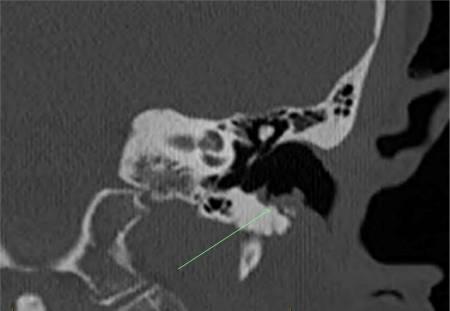

2023年5月,一位耳鼻喉科医生通过耳镜检查发现,患者左外耳道底有侵蚀和骨外露。计算机断层扫描(CT)成像证实了骨侵蚀和软组织改变,支持该诊断(图1)。侵蚀采用保守治疗,每次耳鼻喉科复查时滴入复方康纳乐霜(曲安奈德0.1%+新霉素0.25%+短杆菌肽0.025%+制霉菌素100,000单位/克)。临床诊断为多发性复发性外耳道脓肿(MROEAC),认为是由地诺单抗所致。

图1 病例A—左耳道冠状位CT扫描,箭头显示下耳道侵蚀区域,上覆分叶状软组织